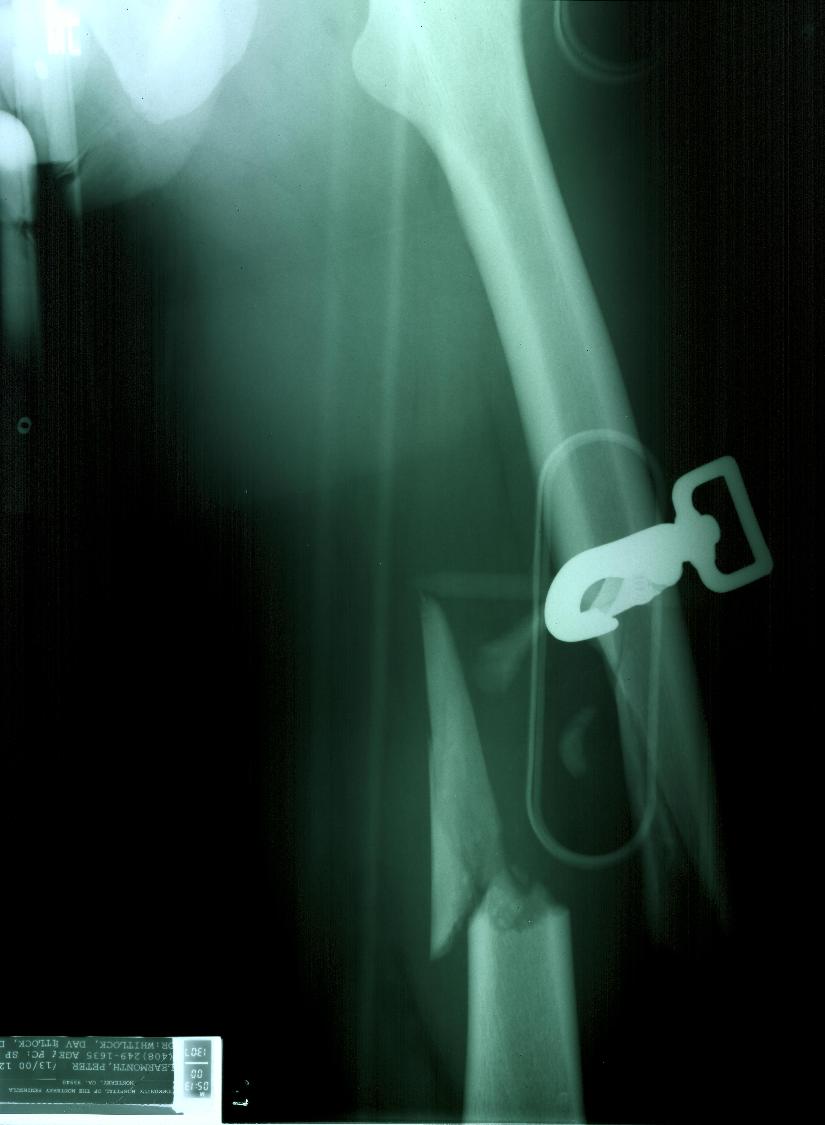

TitaniumLegs 8 #128 July 1, 2003 OK, here's a before shot. The hardware is not from my rig. It's a traction splint. (I know you know that - but others don't.) (>o|-< If you don't believe me, ask me. Quote Share this post Link to post Share on other sites

juanesky 0 #131 July 1, 2003 QuoteOK, here's a before shot. The hardware is not from my rig. It's a traction splint. (I know you know that - but others don't.) Would it be too much to ask about how did it happened? Low turn?"According to some of the conservatives here, it sounds like it's fine to beat your wide - as long as she had it coming." -Billvon Quote Share this post Link to post Share on other sites

TitaniumLegs 8 #135 July 1, 2003 QuoteWould it be too much to ask about how did it happened? Low turn? No, it's not too much. Broken steering line at the bottom of a hook turn. (>o|-< If you don't believe me, ask me. Quote Share this post Link to post Share on other sites